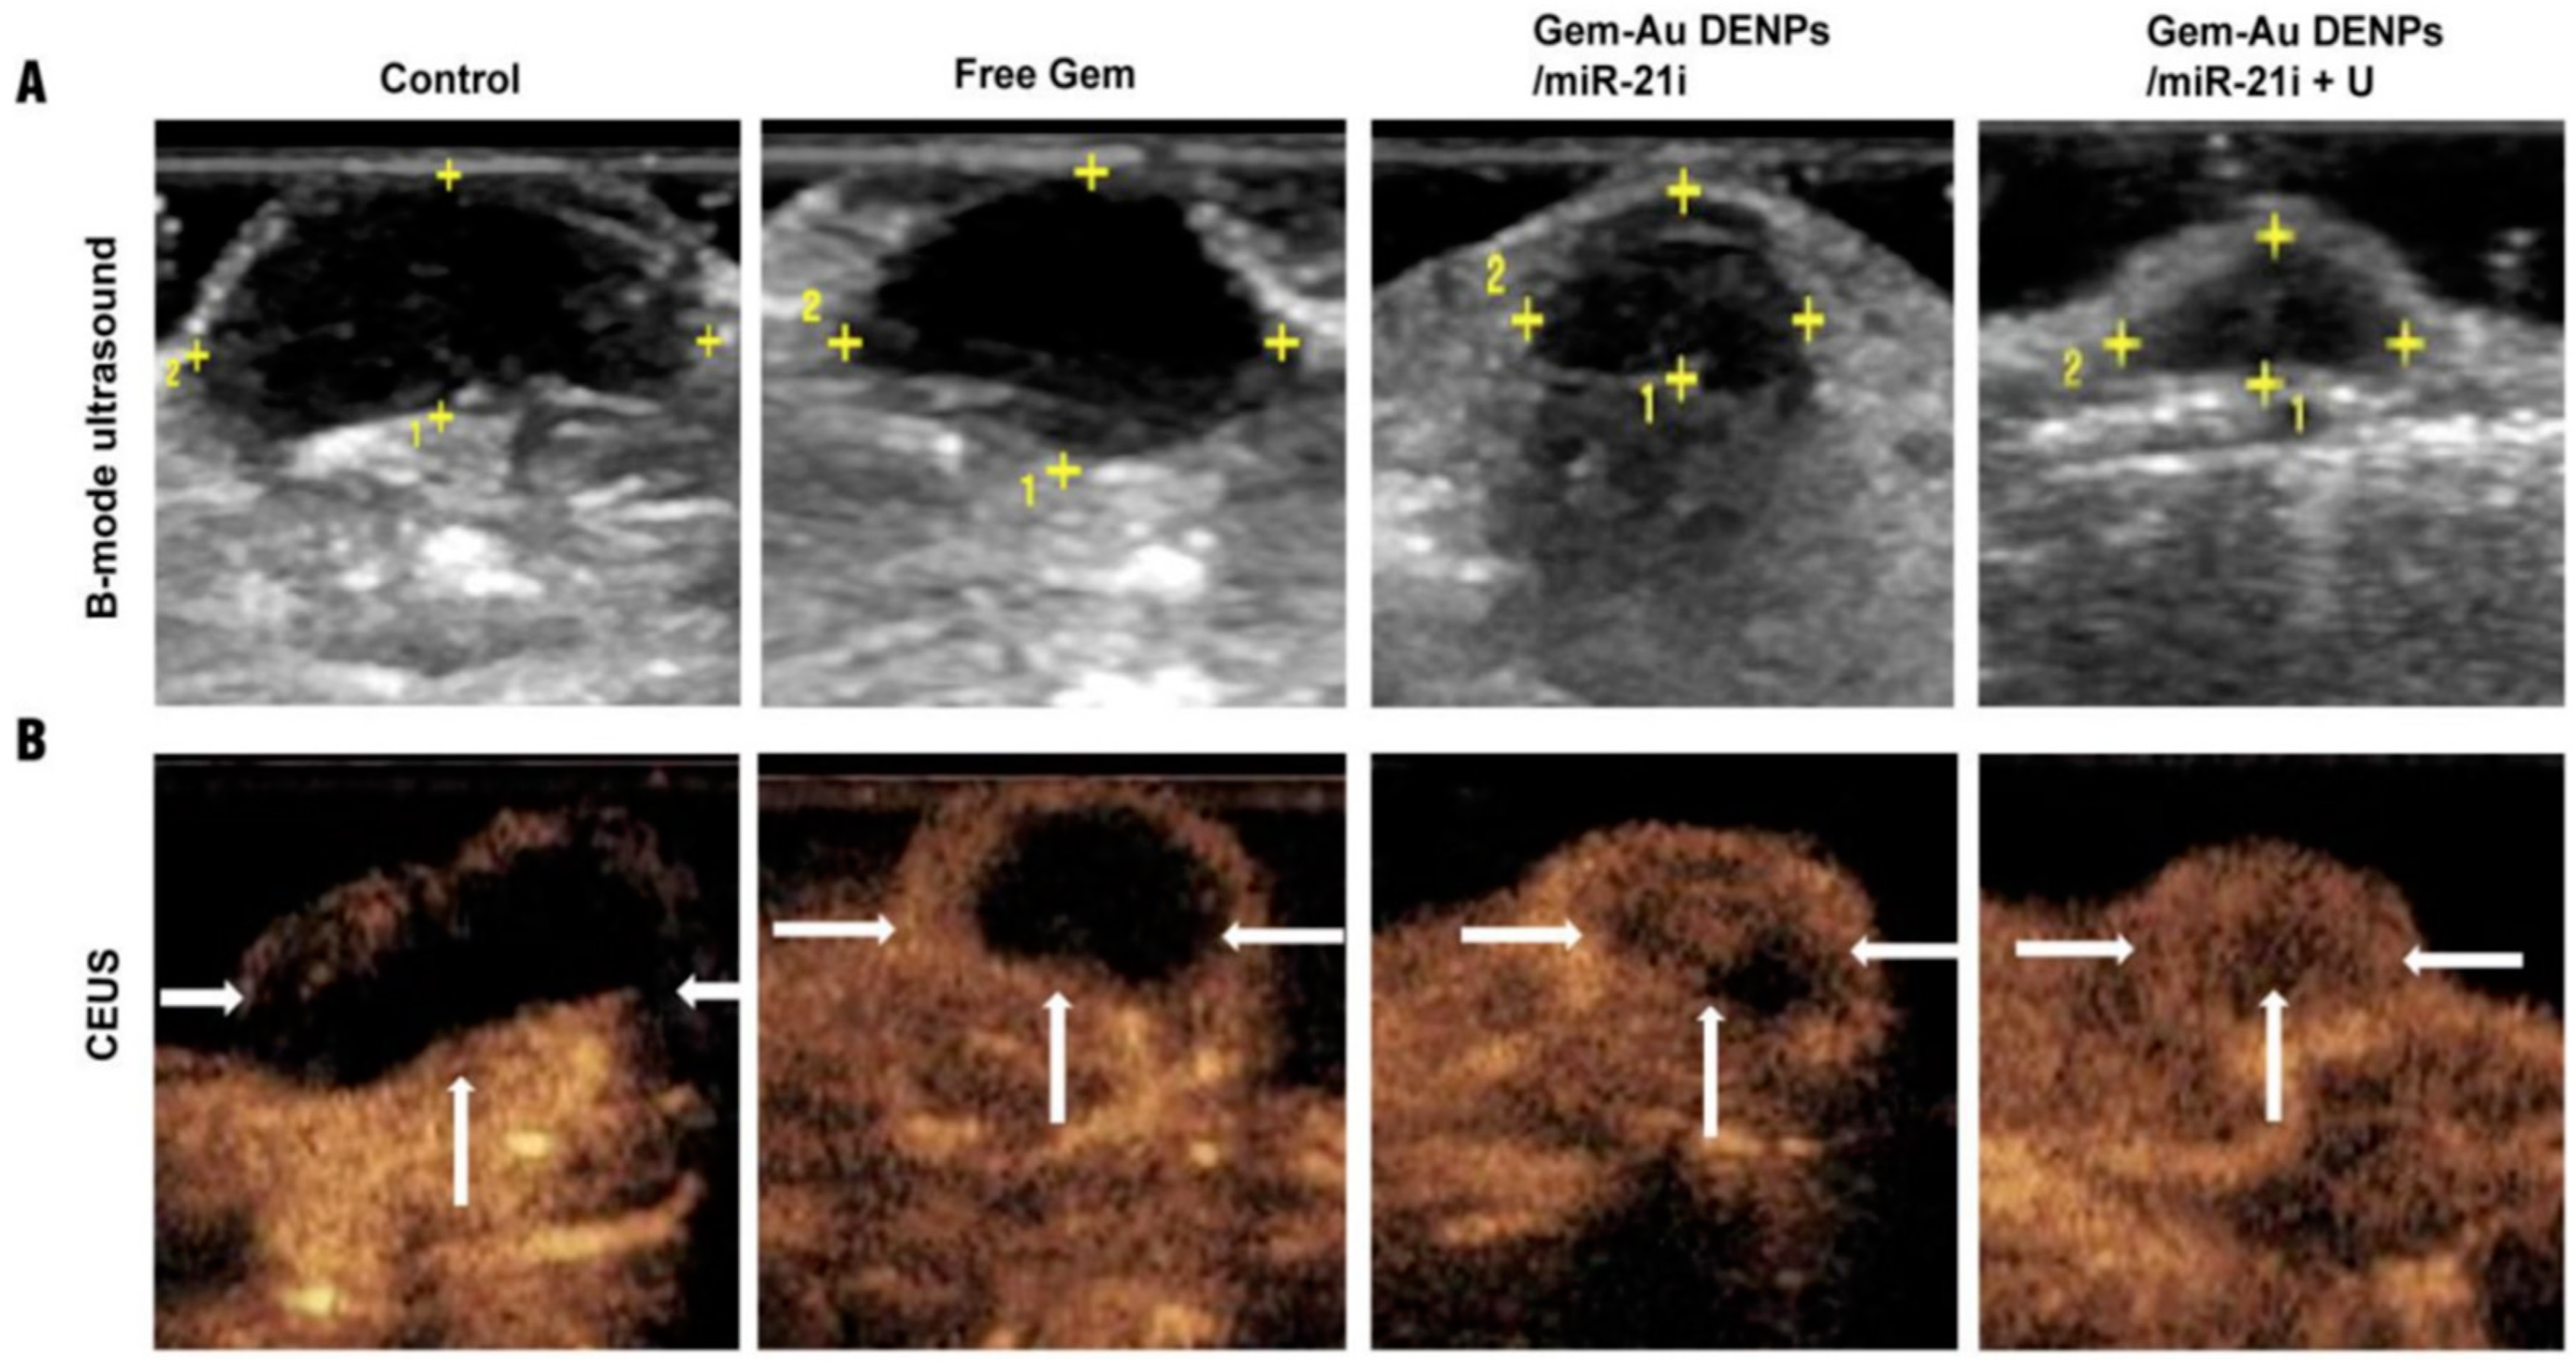

- Lin, L.; Fan, Y.; Gao, F.; Jin, L.; Li, D.; Sun, W.; Li, F.; Qin, P.; Shi, Q.; Shi, X.; et al. UTMD-Promoted Co-Delivery of Gemcitabine and MiR-21 Inhibitor by Dendrimer-Entrapped Gold Nanoparticles for Pancreatic Cancer Therapy. Theranostics 2018, 8, 1923–1939. [Google Scholar] [CrossRef] [PubMed]

| Dendrimer-entrapped gold nanoparticles (AU-DNPs) | Gemcitabine and miR-21 inhibitors | Particle size between 154 to 276 nm | DNA synthesis | Xenografted pancreatic mouse tumors | SW1990 cells | Pancreatic cancer | [136] |